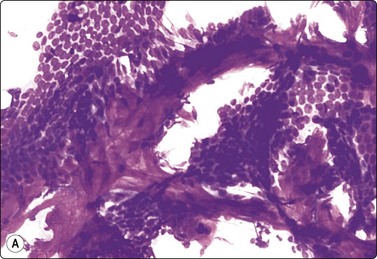

Prominent nuclear atypia shown by a proportion of the epithelial cells is a common phenomenon in fibroadenoma, particularly in young women and women on hormone replacement therapy. The atypia is in the form of nuclear enlargement, anisokaryosis, some irregularity in shape and nuclear chromatin, prominent nucleoli, sometimes a few mitotic figures, and loss of cohesion (Figs 7.24-7.26). The cohesiveness of the epithelial component and relatively bland apearance of epithelial cells should alert against a diagnosis of carcinoma in such cases. Fibroadenoma is the most common cause of false-suspicious and false-positive diagnoses in breast FNB.112-115 In the presence of a clearly benign component of single bipolar nuclei, fragments of bland epithelium, and stroma, a malignant diagnosis should not be made regardless of the degree of atypia shown by a proportion of the epithelial cells. The atypia is most likely hormone related, but a consistent correlation with hormone replacement therapy has not been demonstrated. Proliferative fibrocystic changes and apocrine metaplasia are also common sources of atypia. Histologically, fibroadenomas with severe cytological atypia do not differ from the usual type overall, but focally the duct epithelium may show corresponding nuclear atypia when examined with high magnification (Fig. 7.27). Nevertheless, if prominent atypia is found in FNB smears, a recommendation of excision is advised. Carcinoma can rarely arise in a fibroadenoma. We have seen a few cases of DCIS in fibroadenoma (Fig. 7.28), one with focal invasion. In clinical practice, cytologically typical benign fibroadenomas in postmenopausal patients and fibroadenomas which continue to grow in size are often excised, particularly if the lesion is large.

image

Fig. 7.27 Fibroadenoma

Tissue sections from same case as Figure 7.24; (A) Low power: typical appearances of fibroadenoma; (B) High power: ductal structures lined by atypical epithelium with enlarged vesicular nuclei and a few mitoses (H&E).